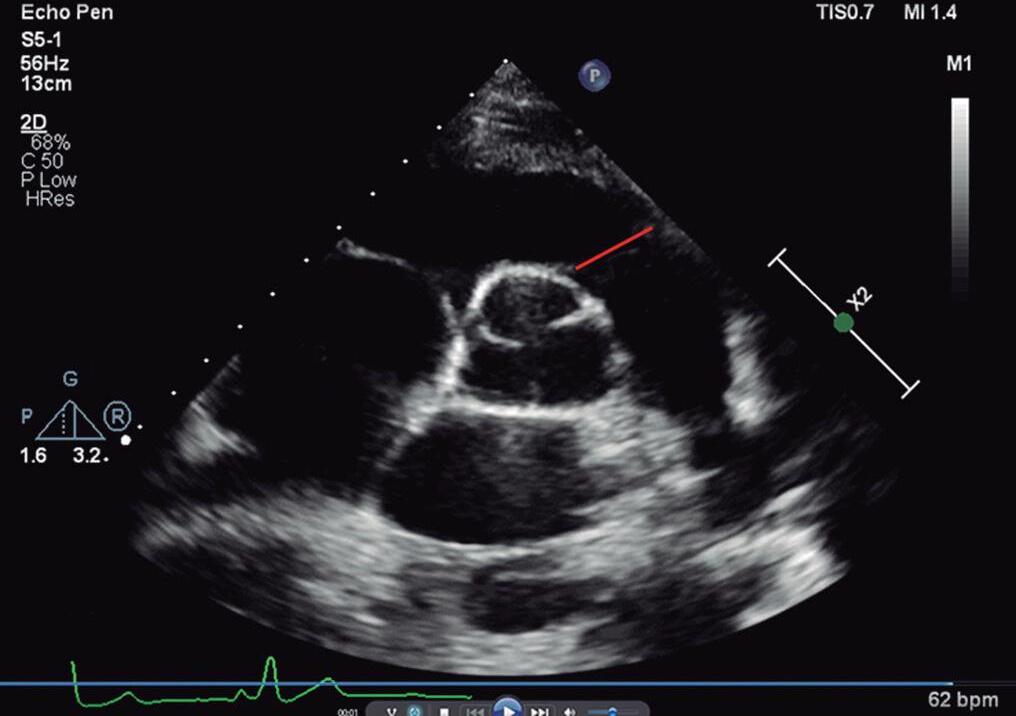

O plano paraesternal pode ser obtido com o paciente em decúbito dorsal ou em decúbito lateral esquerdo. Inicialmente, em geral, obtemos o plano paraesternal eixo longo do VE com o transdutor posicionado na borda esternal esquerda média do paciente e com o index direcionado para o seu ombro direito (Fig. 1-5a e ▶ Vídeo 1-13). Nesse plano, é possível avaliar as vias de saída e entrada do VE e sua contratilidade e mensurar as dimensões das cavidades esquerdas e da aorta (raiz, junção sinotubular e porção ascendente) (Fig. 1-6a; ▶ Vídeos 1-14 e 1-15). Os óstios das artérias coronárias e a continuidade mitroaórtica também podem ser avaliadas. Com discreta movimentação anterior do transdutor, podemos obter o eixo longo do VD e analisar suas vias de entrada e saída (valvas tricúspide e pulmonar) (Fig. 1-6b, c; ▶ Vídeos 1-13 e 1-16).

O mapeamento com Doppler colorido permite avaliar se existe integridade do septo interventricular, disfunções valvares e obstruções da via de saídas ventriculares.

Para obter o plano paraesternal eixo curto, “rodamos” o transdutor no sentido horário com o index apontando para o ombro esquerdo do paciente (▶ Vídeos 1-17 e 1-18). A visão eixo curto das grandes artérias consiste em valva aórtica (posicionada no centro da imagem), via de saída do VD (região infundibulovalvar do VD e artéria pulmonar), valva tricúspide e átrios (Fig. 1-7a e ▶ Vídeo 1-19). Movimentando o transdutor no sentido craniocaudal também é possível obtermos o eixo curto dos ventrículos ao nível dos músculos papilares e da valva mitral para a análise da contratilidade ventricular, do septo interventricular muscular e da valva mitral (Figs. 1-5b e 1-7b, c; ▶ Vídeos 1-17, 1-18, 1-20 e 1-21). O mapeamento em cores é importante para pesquisa de comunicação interventricular muscular e disfunção valvar mitral (Fig. 1-7).

Fig. 1-6. Plano paraesternal eixo longo (2D e Doppler): eixo longo do VE diástole (a) e sístole (b); eixo longo do VD com sua via de entrada (c) e eixo longo do VD com sua via de saída (d). AD: átrio direito; AE: átrio esquerdo; VD: ventrículo direito; VE: ventrículo esquerdo; Ao: aorta; M: valva mitral; AP: artéria pulmonar; VT: valva tricúspide; VP: valva pulmonar; AP: artéria pulmonar; SIV: septo interventricular.